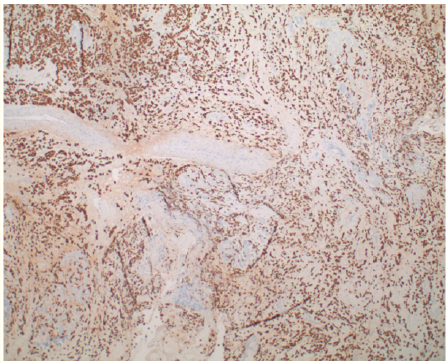

Rare Presentation of Metastatic Lobular Mammary Carcinoma to the Orbit

F Rhana Mousavi, Mina Bekheit, Nick A Hirad, Nicki Hirad and Abanoub Gabra. 6(9): 01-05.